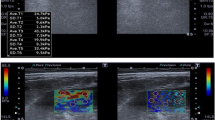

Top: Representative images and quantification of trichrome staining from contralateral medulla. SW ameliorated the increased medullary fibrosis in ARAS CLK. Bottom: Representative MRE images (yellow/red color indicates greater stiffness) from contralateral cortex and medulla (TIFF 2309 kb)